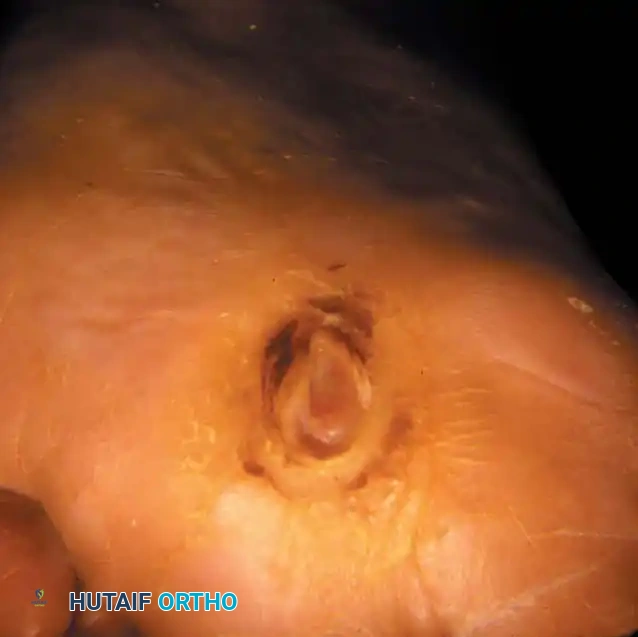

- Grade 2: Deep ulcer penetrating to tendon, bone, ligament, or joint capsule.

- Grade 3: Deep abscess, osteomyelitis, or pyarthrosis.

* Depth II: Ulceration extending to the tendon and joint capsule, but bone/joint is not visible.

* Depth III: Exposed bone or joint, implying contiguous osteomyelitis or pyarthrosis.

For Grade 2 and Grade 3 ulcers, aggressive surgical debridement is the cornerstone of therapy. The goal is to convert a chronic, contaminated wound into an acute, clean wound.

3. Soft Tissue Debridement: Excise all hyperkeratotic margins, fibrotic tissue, and necrotic fascia until healthy, bleeding tissue is encountered.

6. Closure: Leave the wound open to heal by secondary intention, or apply a negative pressure wound therapy (NPWT) device. Primary closure is contraindicated in the presence of active infection.